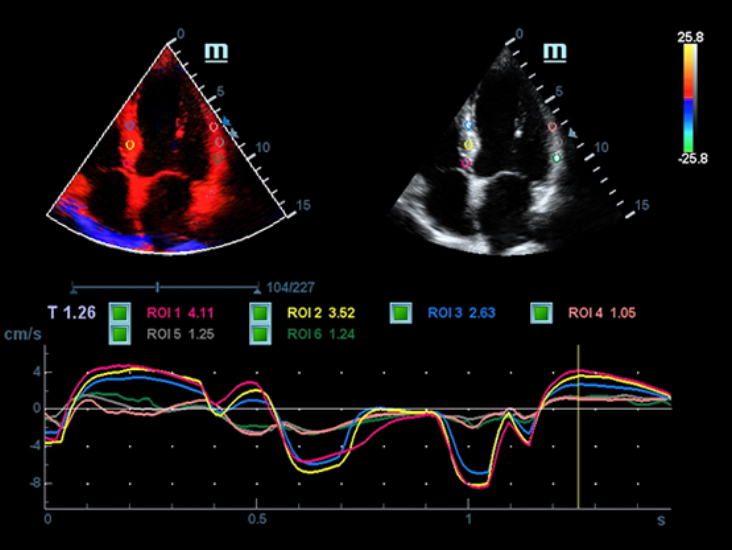

X-Insight is an insightful solution to envision more.

MindrayŌĆÖs brand-new solution is an excellent fusion of continuous customer insights into clinical needs, combined with continually evolving cutting-edge ultrasound technologies. Full of vitality, with the goal of insight into the future and pursuit of the infinity, it is constantly improving with increased scalability.

Based on the deep insights of customer needs, the DC-60 ECHO with X-Insight is designed to deliver high efficiency with precision imaging, which is empowered by eXpress Clarity, eXceptional Intelligence and eXceeding Experience.